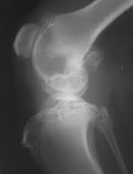

骨髄炎は骨の感染症です。感染は血流を介して骨に達したり、周囲の組織から広がったりします。この感染症は黄色ブドウ球菌が原因であることが最も多い。骨の感染症は突然起こることもあれば、長期間にわたって起こることもあります。適切な治療が行われないと...

骨髄炎は骨の感染症です。感染は血流を介して骨に達したり、周囲の組織から広がったりします。この感染症は黄色ブドウ球菌が原因であることが最も多いです。骨の感染症は突然起こることもあれば、長期間にわたって起こることもあります。適切な治療が行われな...